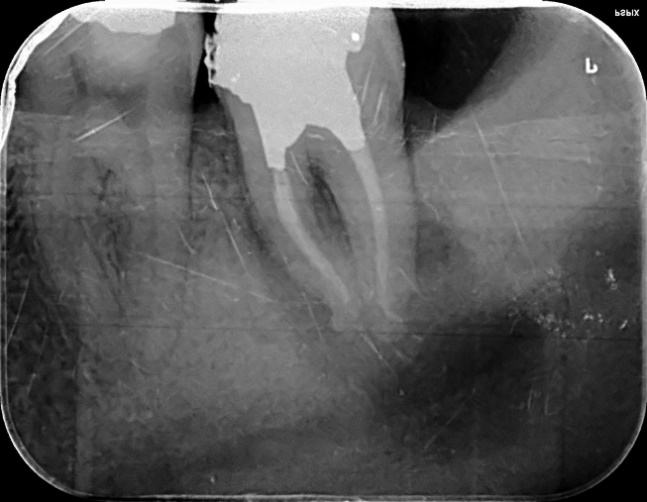

Upper Premolar curved root Primary root canal treatment